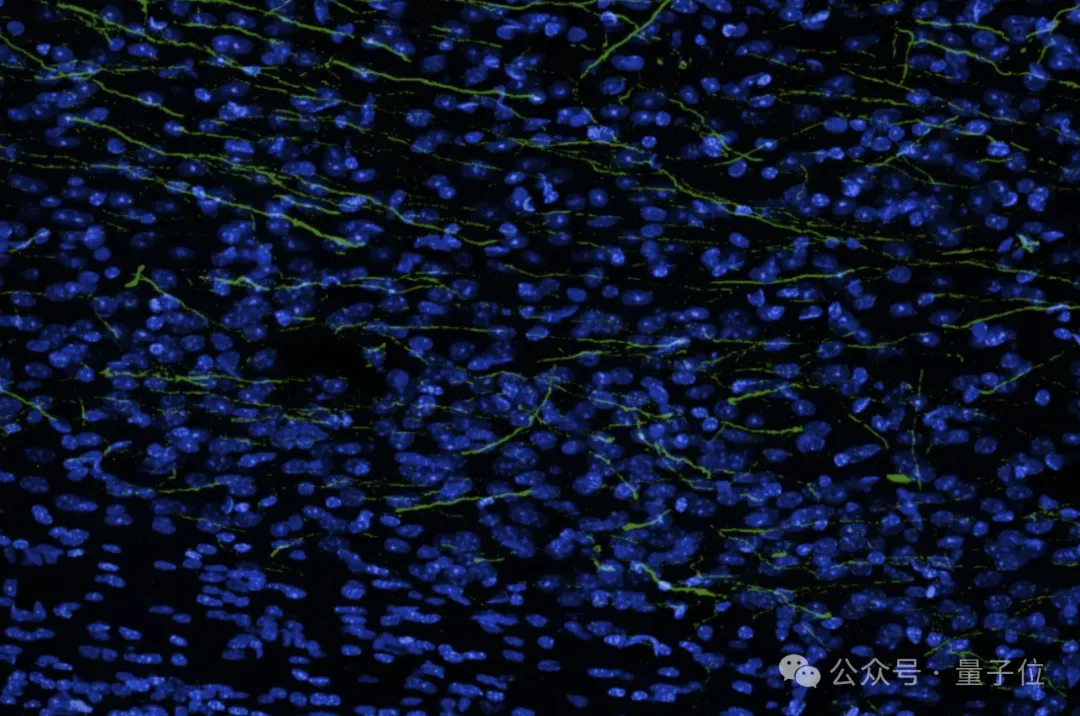

如图所示,绿色突出显示的细胞是实际的神经元轴突和树突,它们从生物混合移植物中延伸出来,在整个大脑中形成能够传输信息的连接。